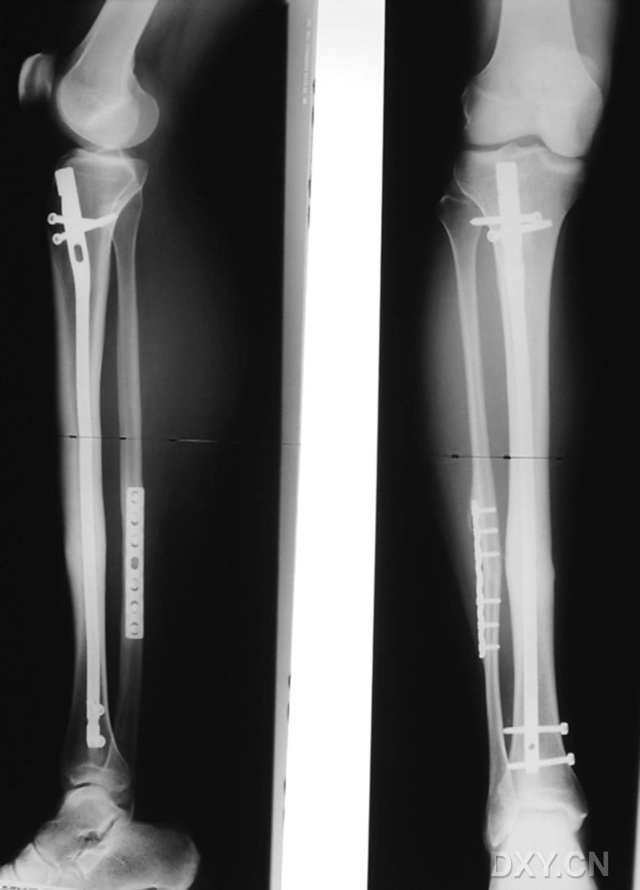

圖2 患者男性,51歲,骨折時仍吸煙,術后9個月的X線片顯示骨折呈萎縮型不愈合。